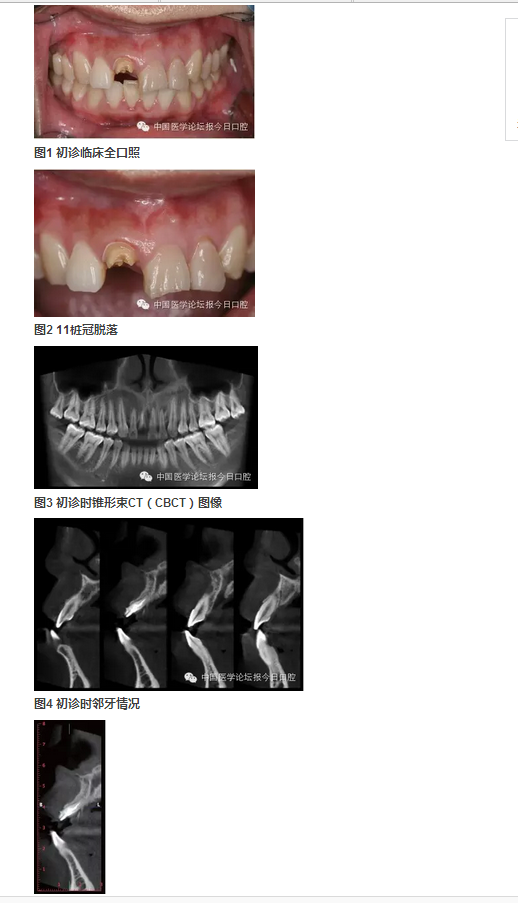

女性,27歲。以“右上前牙樁冠修復11年,脫落1周”為主訴前來就診。

11年前,患者前牙外傷,于當?shù)蒯t(yī)院行11、21、22根管治療及11樁冠修復。1周前11樁冠脫落,于多家醫(yī)院修復科就診,以“11牙槽突骨折”的診斷,無法保留11殘根,建議拔除,而前來就診。

臨床檢查可見11殘根,21、22牙冠變色。前牙區(qū)咬合略緊,Ⅱ度深覆牙合。CBCT示上頜右側(cè)中切牙頰側(cè)根頸1/3骨板折裂。21、22牙冠變色。前牙區(qū)咬合略緊,Ⅱ度深覆牙合。CBCT示上頜右側(cè)中切牙頰側(cè)根頸1/3骨板折裂。21、22根尖病變,前牙區(qū)牙槽突根方骨量不足。

圖6 舌側(cè)骨缺損的3D重建

①右上中切牙牙槽突骨折(?);② 左上中切牙、側(cè)切牙慢性根尖炎;③Ⅱ度深覆牙合。

病例特點與難點

①樁冠修復失敗后的三維骨缺損(頰/舌側(cè)骨板折裂、牙槽骨根方骨量不足);②年輕女性,美學要求較高;③ 鄰牙根尖周病變;④輕度深覆牙合,咬合略緊。上頜骨基底骨骨量不足,正畸醫(yī)師不建議矯正。